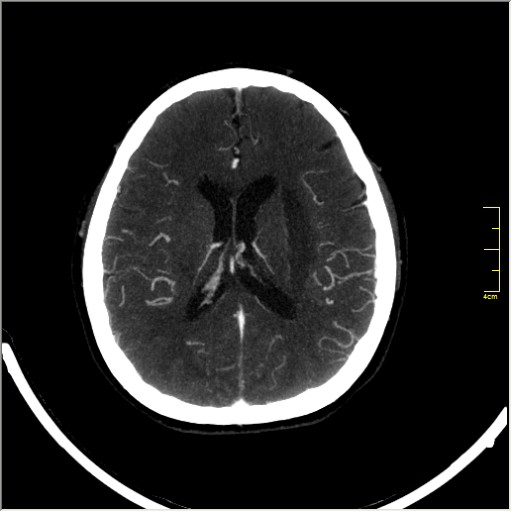

КТ ангиография головного мозга

Стандартная процедура в современной работе КТ кабинета, весьма несложна в исполнении.

Сканы представленны в режиме MIP.

Angio0.JPG

Angio1.JPG

Angio2.JPG

Angio3.JPG

Angio4.JPG